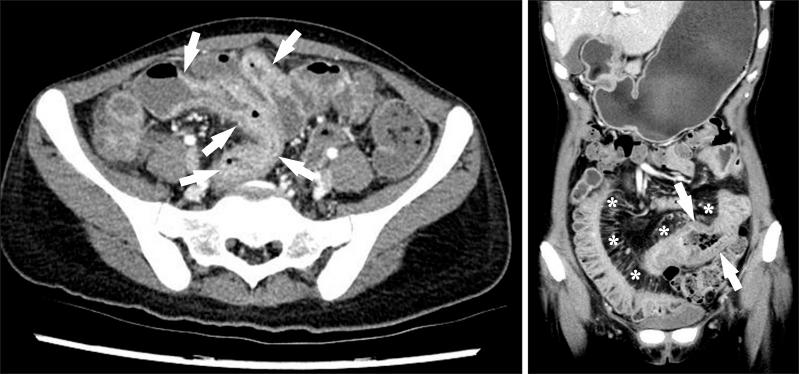

Imaging of the small bowel is complicated by its length and its overlapping loops. Recently, however, the development of crosssectional imaging techniques, such as computed tomography enterography (CTE) and magnetic resonance enterography (MRE) has shifted fundamental paradigms in the diagnosis and management of patients with suspected or known Crohn's disease (CD). CTE and MRE are noninvasive imaging tests that involve the use of intraluminal oral and intravenous contrast agents to evaluate the small bowel. Here, we review recent advances in each cross-sectional imaging modality, their advantages and disadvantages, and their diagnostic performances in the evaluation of small bowel lesions in CD.